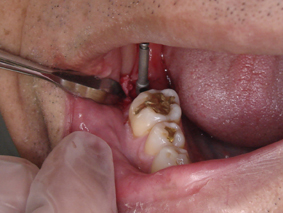

DSC01674.JPG

このインプラントにネジで上部構造を固定します

既製品ではなく、カスタムメイドで上部構造を作る方法もありますが、今回は既製品を使ってみることにしました

本当はもう少し太いタイプを使うほうが良いと思います

DSC01677.JPG

ねじ込んでいるところです